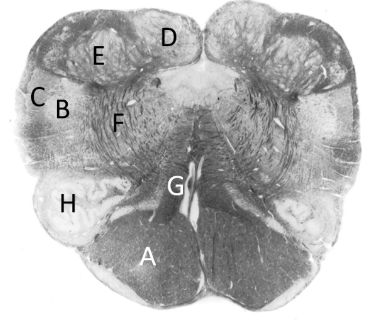

at what level is this?

mid-medulla

what is a?

inferior cerebellar peduncle

what is b?

medial lemniscus

what is c?

pyramidal tract

what is d?

inferior olivary nucleus (m)

what is e?

hypoglossal nerve fibres

what is f?

inferior vestibular nucleus

what is g?

medial vestibular nucleus

what is h?

dorsal nucleus of vagus

what is J?

median longitudinal fasciculus

what is k?

hypoglossal nucleus

what is L?

olivocerebellar fibres

what is m?

olive

what is n?

4th ventricle (m)

what is o?

solitary tract